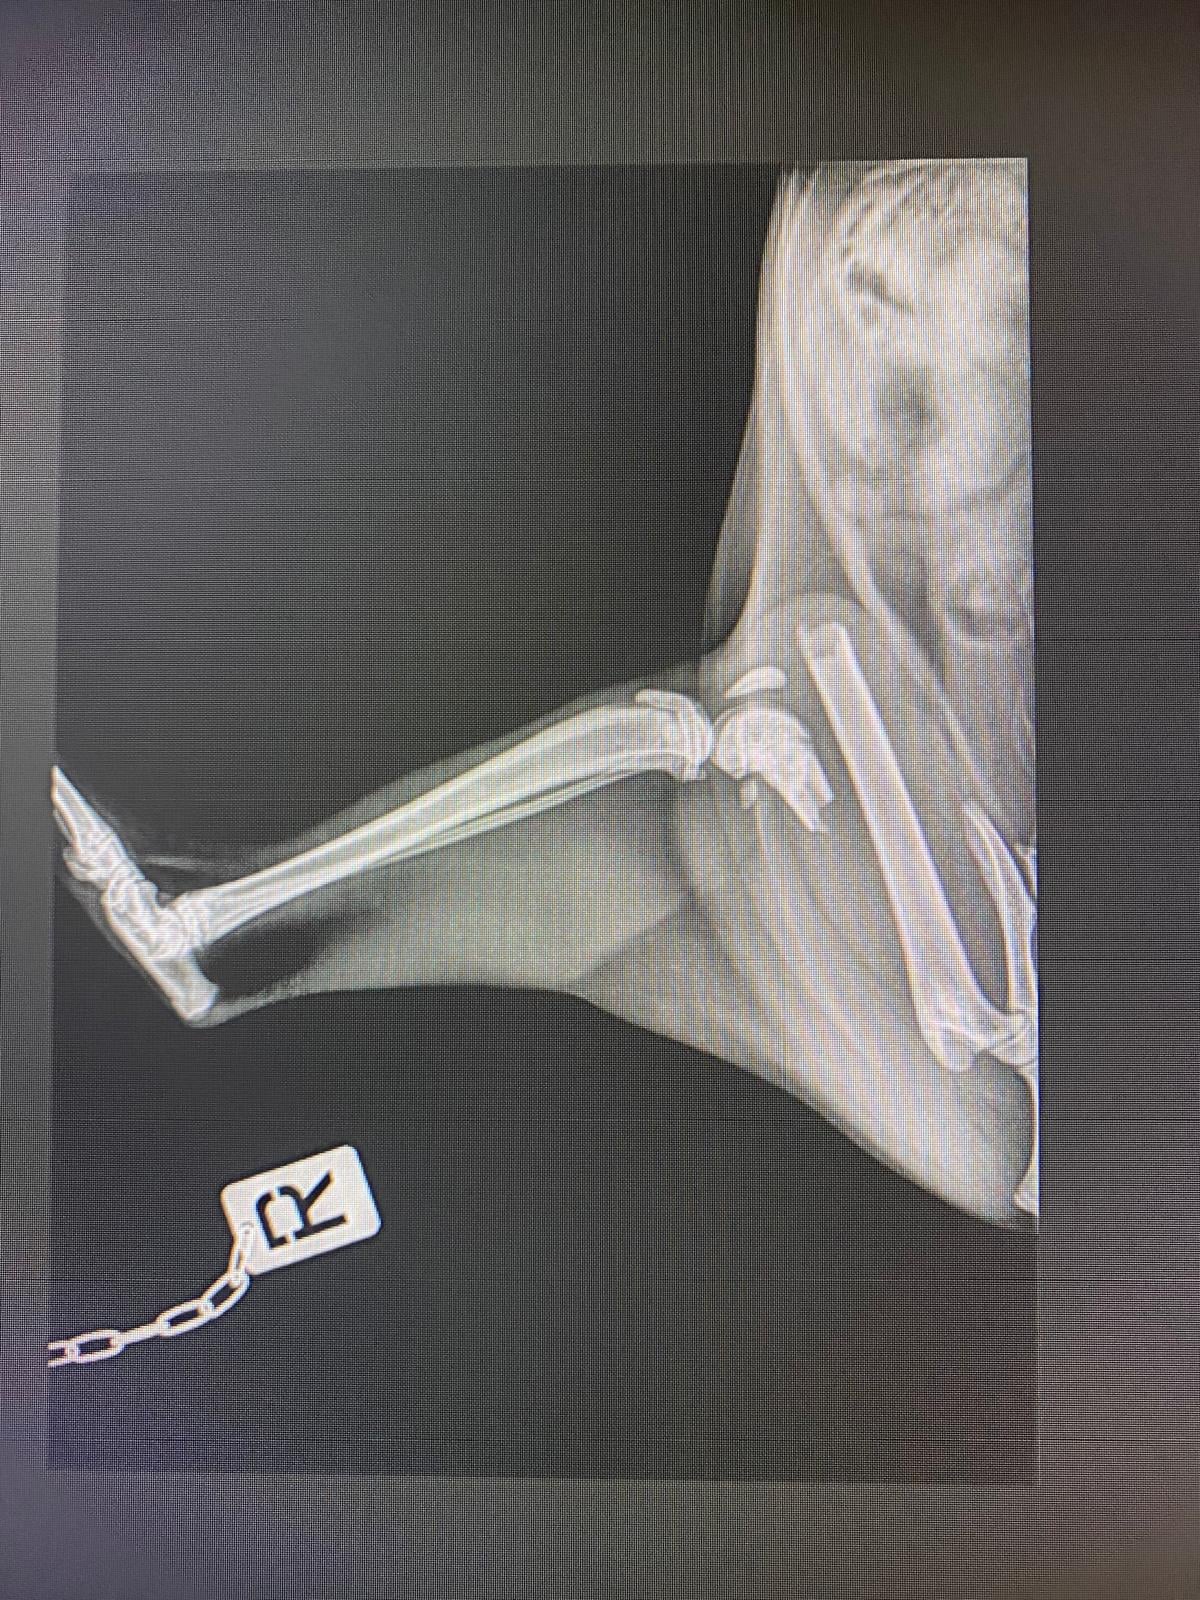

Dulcinea es una gatita de solo 6 meses , la han abandonado con una fractura tremenda, necesita una operación urgente, nos han dado presupuesto (882,84€) y no sabemos cómo hacer frente a este gasto tremendo.